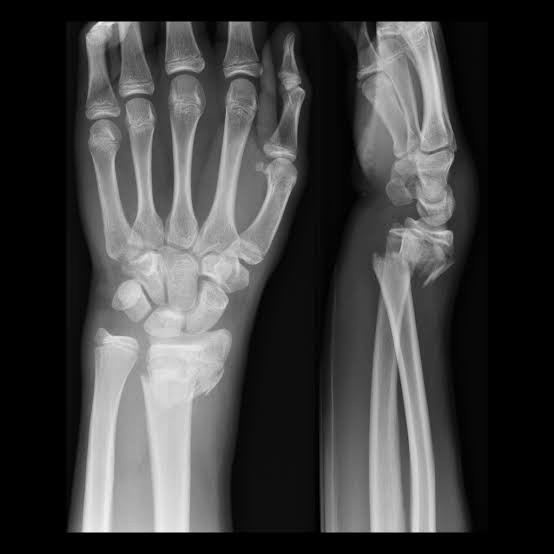

2  จงให้การวินิจฉัยในผู้ป่วยรายนี้